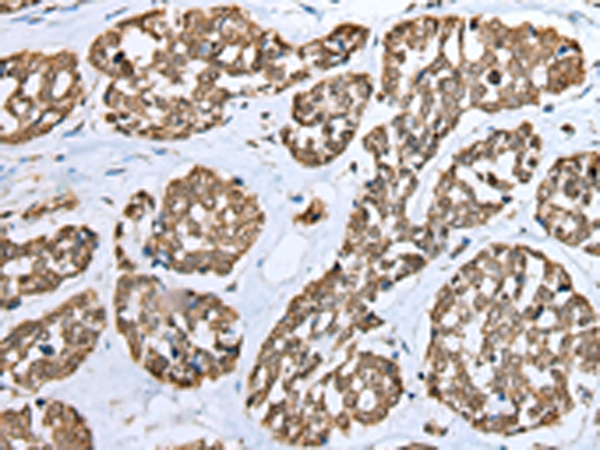

分类: 科研抗体货号: P02152别名: ED3; EDA3; ECTD11A; ECTD11B应用: IHC反应种属: Human